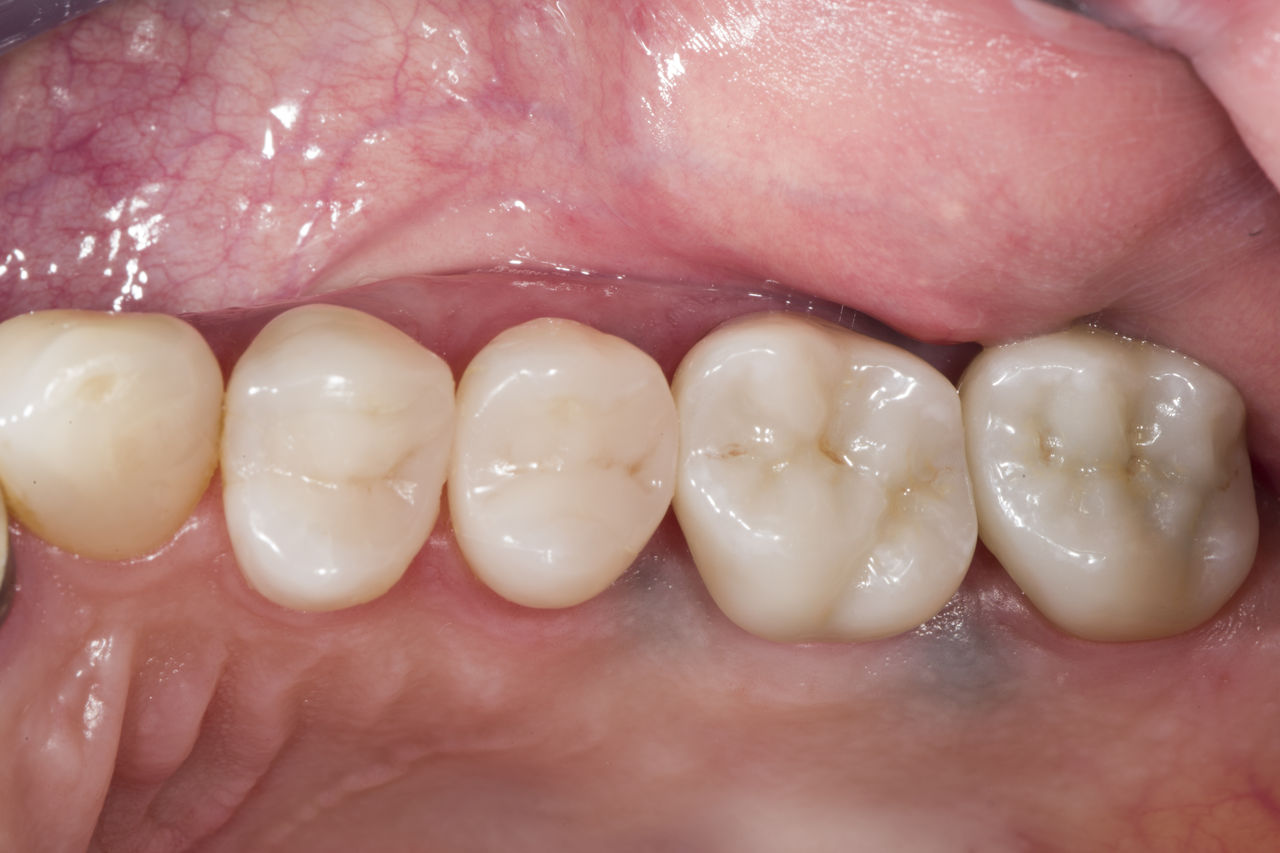

Réhabilitation du quadrant

Deux couronnes CEREC Tessera et deux inlays

En une seule visite de quatre heures, la restauration de deux couronnes et de deux inlays, vieux de 15 ans, a été réalisée. La patient était très satisfaite du très bon résultat esthétique.

Avant : Plombages insuffisants dans le deuxième quadrant. Les restaurations avaient environ 15 ans.

Après : Couronnes fabriquées en consultation à partir du CEREC Tessera (dents 26/27). Inlays pour les dents 24 et 25 en blocs de composite.

Dr Andreas Bindl

Zurich, Suisse